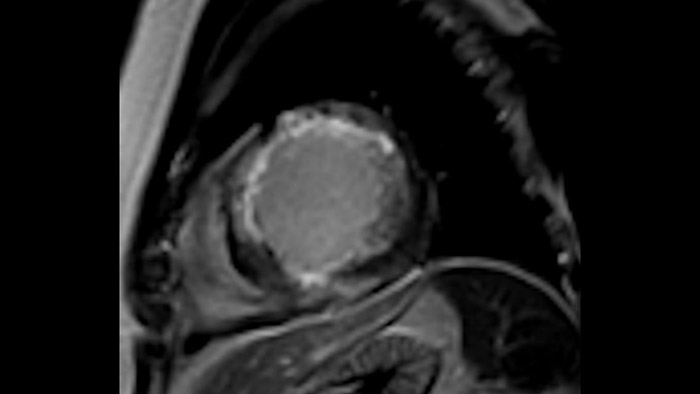

Os diagnósticos tradicionais não têm a visibilidade necessária para ver os efeitos do tratamento cardíaco ou para detetar disfunção antes que os sintomas ocorram. Ao combinar a sequência de aquisição de RM da Philips Fast-SENC com a ferramenta de análise MyoStrain da Myocardial Solutions, as alterações precoces e subtis da função cardíaca podem ser medidas diretamente.